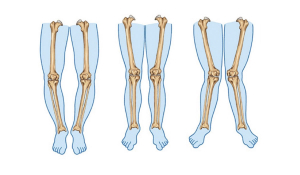

Коригуюча остеотомія: відновлення руху та якості життя

В сучасному світі, де здоров'я та якість життя є важливими пріоритетами для кожної людини, інноваційні методи лікування стають все більш популярними. Одним із них є коригуюча остеотомія - хірургічна процедура, яка дозволяє виправити вроджені або набуті деформації кісток, забезпечуючи відновлення функцій та поліпшення рухової активності.